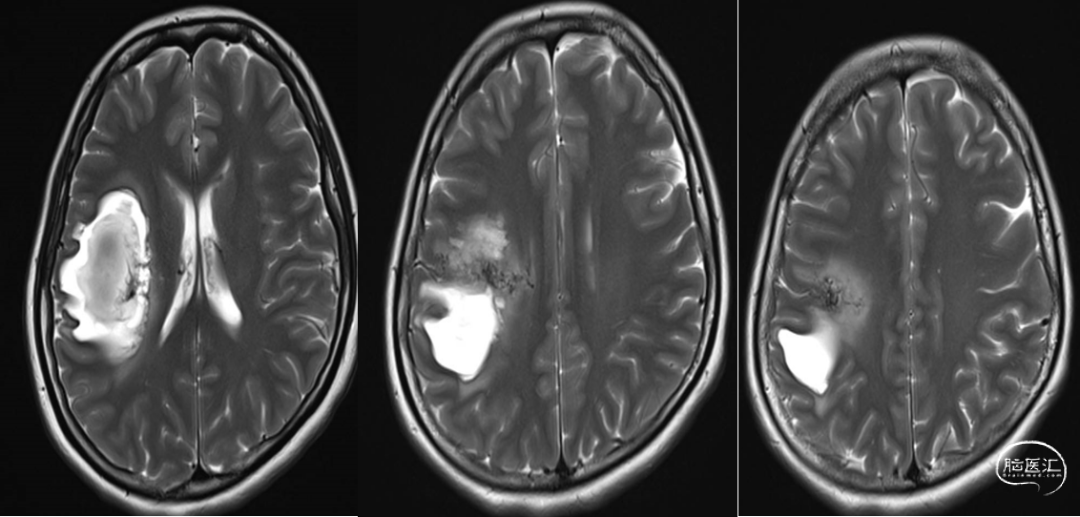

我院磁共振

DSA:右侧额顶叶脑动静脉畸形